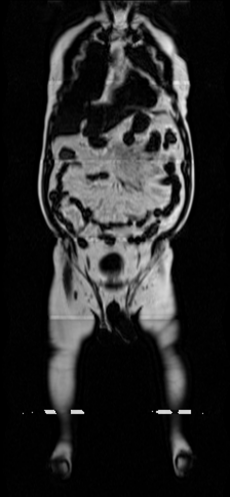

Our results unequivocally highlight the superior performance of X-Diffusion in terms of both qualitative and quantitative metrics. Representative MRI volumes generated by our pipeline, when juxtaposed with ground-truth images, showcased remarkable similarity, with even intricate physiological features like tumor information, spine curvature, and fat distribution being accurately captured.

Notably, X-Diffusion achieves sota dB for a few input slices while baselines require more than 60 input slices to achieve similar performance (Figure 7). The margin is more than 12 dB PSNR for the 1-slice input in both the BRATS and the UK Biobank benchmarks (see Table 1 and Figure 6). For reference, two randomly sampled MRIs from the UK Biobank would have a PSNR of 15.95 dB 0.36 (on 4800 randomly sampled examples). The slices from 3D reconstructed volumes at varying depths and axis of rotation visually match the ground truths (see Figures 5 and Figure 4). We also plot the error map (Figure 4) of such X-Diffusion generations to highlight the differences with the ground truth MRIs.

Preservation of Spine Curvature. For the spine segmentation on UK Biobank, we use a UNet++ model [81] with Dice Loss and use the curvature prediction of the spine followed in [9]). We measure the Pearson correlation factor [9] of spine curvature measured on the generated MRIs where the input is a single MRI coronal slice, or a single sagittal slice against the curvature of reference real MRIs of the same samples. The correlation coefficients are 0.89 for the coronal MRIs and 0.88 for the sagittal MRIs on the test set of 308 human-annotated angles.